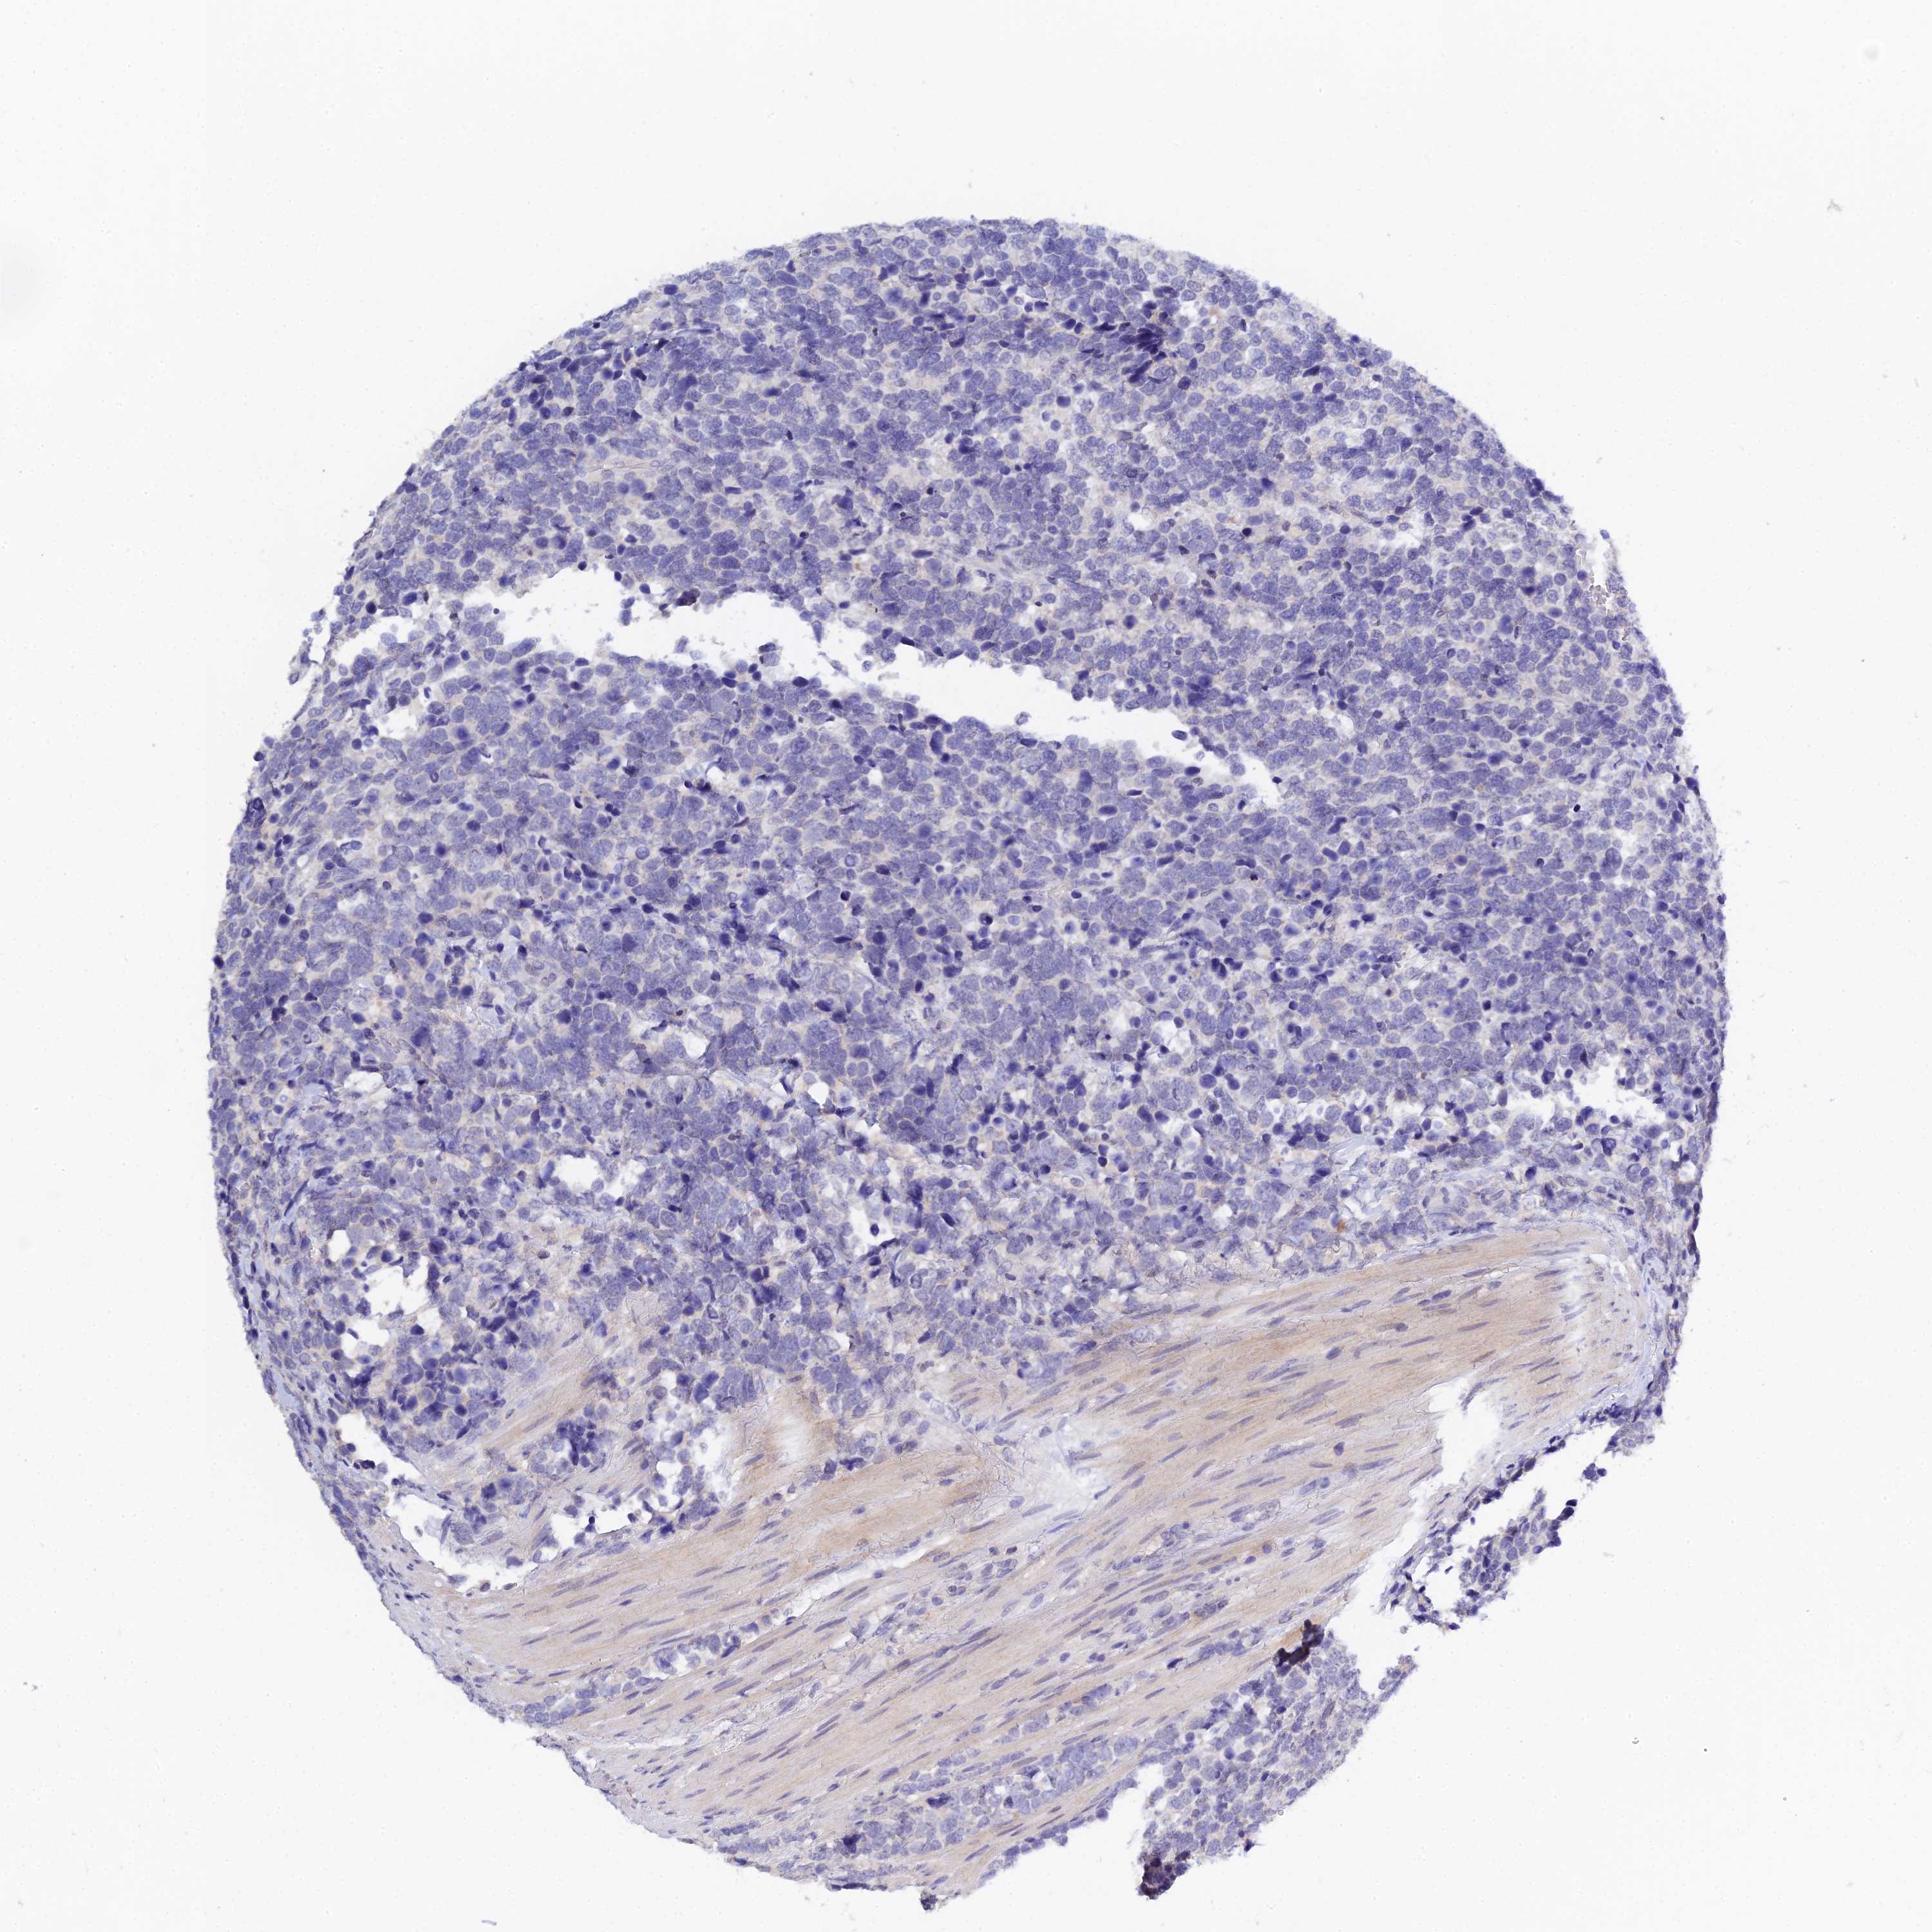

UROTHELIAL CANCER - Protein expressioni

A mouse-over function shows sample information and annotation data. Click on an image to view it in a full screen mode. Samples can be filtered based on level of antibody staining by selecting one or several of the following categories: high, medium, low and not detected. The assay and annotation is described here.

Antibody stainingi

Antibody staining in the annotated cell types in the current human tissue is reported as not detected, low, medium, or high, based on conventional immunohistochemistry profiling in selected tissues. This score is based on the combination of the staining intensity and fraction of stained cells.

Each image is clickable and will lead to virtual microscopy that enables deeper exploration of all samples and also displays staining intensity scores, fraction scores and subcellular localization as well as patient and tissue information for each sample.

Antibody HPA044576

Staining

High

Medium

Low

Not detected

Intensity

Strong

Moderate

Weak

Negative

Quantity

>75%

75%-25%

<25%

None

Location

Nuclear

Cytoplasmic/membranous

Cytoplasmic/membranous,nuclear

Urothelial carcinoma, High grade

Urothelial carcinoma, Low grade

Urothelial carcinoma, NOS